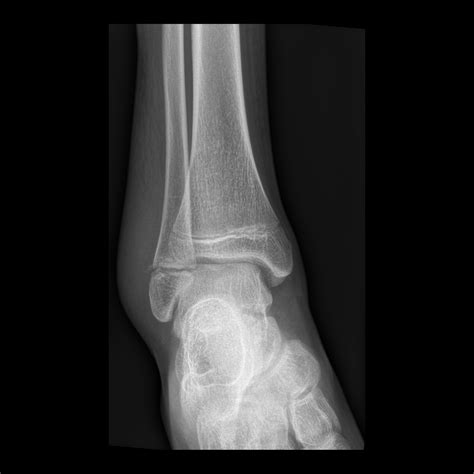

Pediatric Radiology is a subspecialty of radiology focused on the imaging of infants, children, and adolescents. Because children are not simply "miniature adults," their bodies undergo constant growth and development. Bones are still ossifying, organ systems are maturing, and metabolic rates are significantly higher than those of adults. These factors necessitate highly specific protocols for diagnostic imaging.

• X-rays: Often the first line of defense for bone fractures or lung issues.

X-ray Minimal Bone fractures, pneumonia, chest congestion

Furthermore, radiation sensitivity is a biological reality in younger patients. Because children have a longer life expectancy, the theoretical risk associated with cumulative radiation is handled with extreme caution. Specialized radiologists use dose-reduction software and settings tailored specifically to the body size of the patient, ensuring that the child receives the lowest effective dose of ionizing radiation possible.